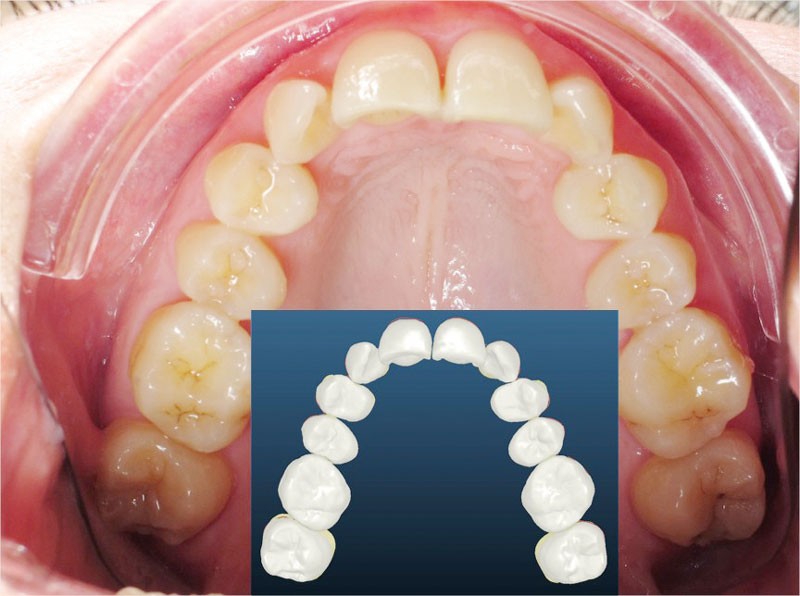

Un appareillage Damon métal a été mis en place, réalisé à partir d’un set up numérique Insignia pour obtenir un contrôle précis des torques et de la forme d’arcade et réduire le temps de finition grâce à un collage indirect très précis.

De larges surélévations postérieures étalées ont été mises en place et la patiente a porté des élastiques précoces suivant les principes de la technique Damon. Les 14 et 24 rempliront le rôle des 13 et 23.

L’objectif, en utilisant la technique Insignia est de réduire le temps de traitement de 28 à 18 mois avec 12 rendez-vous (fig. 5 à 14).